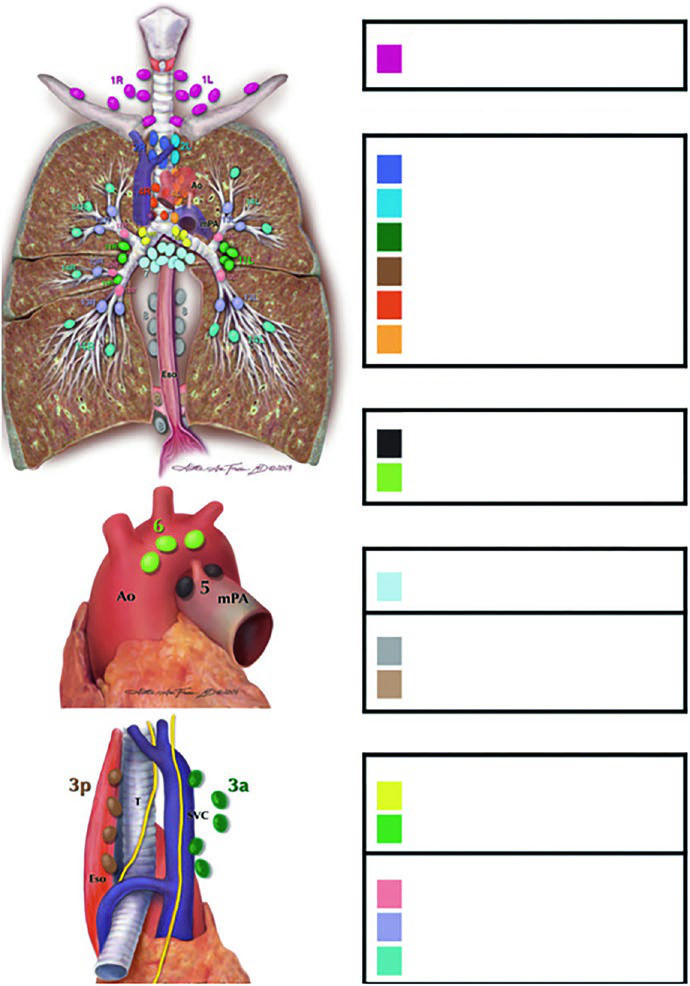

Estações linfonodais: atlas de Michigan como referência

Todo planificador que trabalha com pulmão precisa dominar o atlas linfonodal de Michigan. Sem esse mapa mental, as decisões sobre campo envolvido versus eletivo se tornam arbitrárias.

As estações são organizadas em zonas anatômicas:

- Supraclavicular: Estação 1

- Mediastino superior: 2R, 2L, 3a, 3p, 4R, 4L

- Aórtica: 5, 6

- Mediastino inferior: 7, 8, 9

- N1 (intrapulmonares): 10, 11, 12, 13, 14

A tabela abaixo, baseada nos dados da Figura 13.1b do capítulo, mostra o risco de acometimento por estação conforme a localização do tumor primário. Esses percentuais orientam a decisão de incluir ou excluir regiões eletivas do campo.